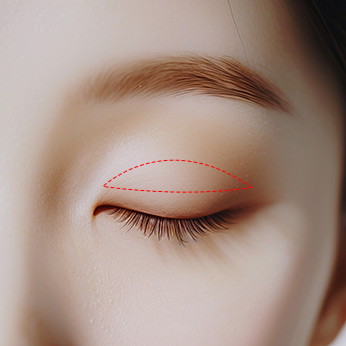

<div class="full_img" data-delay="1" data-direction="bottom">

<div class="pc_only"><img src="../img/eye/03_01.jpg" alt=""></div>

<div class="mb_only"><img src="../img/eye/03_01_m.jpg" alt=""></div>

<span>눈매교정 개선 부위</span>